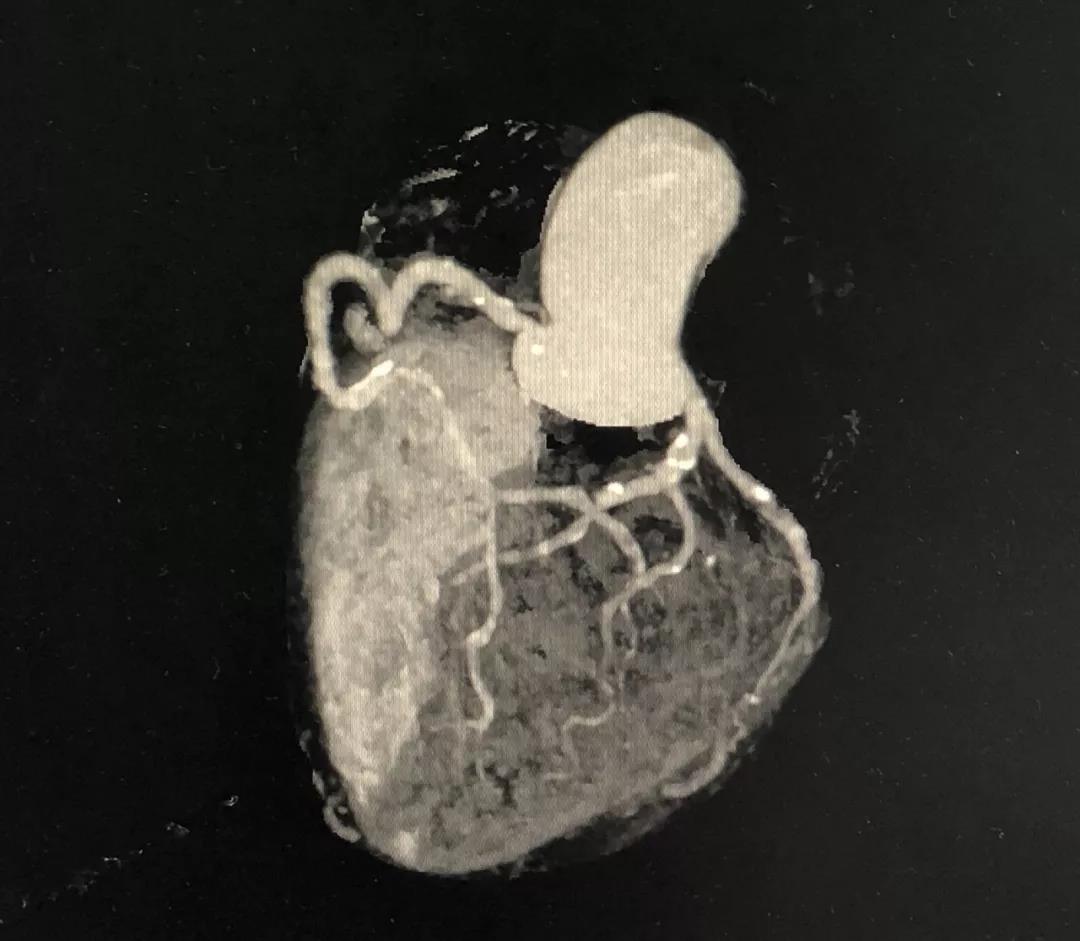

冠状动脉CTA

CCTA LCX病变特点:

LM前分叉正常

LCX相对较直

中段病变伴局灶点状钙化

处理策略:

PTCA+药物涂层支架(DES)

CCTA的指导价值

药物洗脱球囊最核心的操作要领:一是充分的斑块预处理,二是药物球囊迅速到达目标病变位置,从而实现最有效的药物定点释放。其中,CCTA的评估功能不容小觑。结合上面的病例,术前CCTA检查的必要性如下:

5、左主干无钙化,前分叉正常,为选用7F指引导管和/或使用延长导管提供了机会。